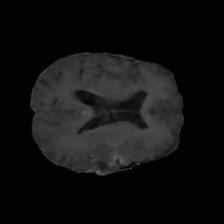

Brain tumor segmentation. Segmenting tumors in brain is challenging due to the high variance in appearance and shape of the tumors [28]. We use a subset of the 2017 Brain Tumour Image Segmentation (BraTS) dataset [29, 26]. It contains multi-parametric 3D MRI scans. The segmentation masks include (possibly overlapping) three classes of tumor. The 3D scans are split into 2D image slices, and only images that contain at least one tumor class are retained. Figure 7 shows three MSGNet generated samples as well as the corresponding masks. Since MSGNet adheres to the underlying relationships between various classes, we see that the generated images and the masks for different tumor classes are in line with the images and masks from the training set. In general, MSGNet rarely generated erroneous samples; we found roughly one sample per 3000 generations that could be rejected. Similar to the malaria experiment, we observed an improvement of 3.1% () in -score on the validation set.

A subset of the BrATS dataset was used. We used the images accompanied by segmentation layouts from the FLAIR and T1Gd modes. The segmentation layouts showed the sub-regions for three different classes: GD-enhancing tumor, the peritumoral edema, and the necrotic and non-enhancing tumor core. The brain and the background were treated as an additional class. We refer to [32] for further details. For the two modes, the background has been modelled using two different classes. We only considered half of the 155 slices, i.e., we took only the even-numbered slices and out of those we discarded the slices that did not include one of the previously mentioned tumor-classes in order to create a more balanced dataset. This resulted in 20,000 images that were further augmented with 6,000 MSGNet generated images. Example generations of the masks as well as the images are shown in Figure 12.